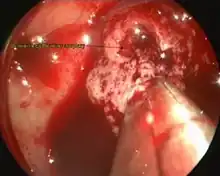

The decision on whether to surgically decompress the pituitary gland is complex and mainly dependent on the severity of visual loss and visual field defects. If visual acuity is severely reduced, there are large or worsening visual field defects, or the level of consciousness falls consistently, professional guidelines recommend that surgery is performed.[6] Most commonly, operations on the pituitary gland are performed through transsphenoidal surgery. In this procedure, surgical instruments are passed through the nose towards the sphenoid bone, which is opened to give access to the cavity that contains the pituitary gland.[6][9] Surgery is most likely to improve vision if there was some remaining vision before surgery,[9] and if surgery is undertaken within a week of the onset of symptoms.[9][16]